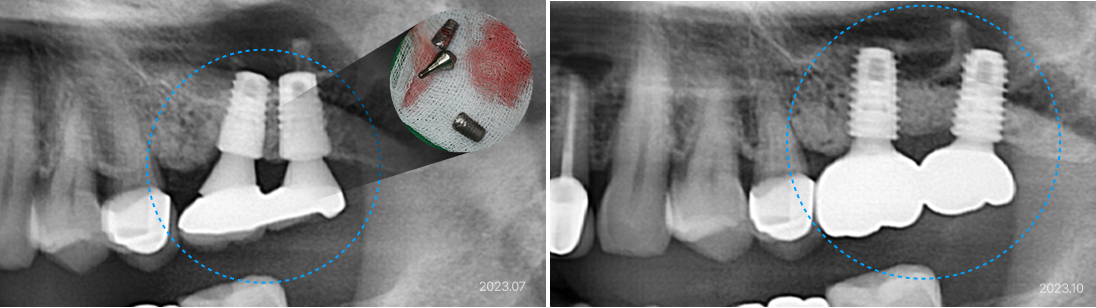

63세, 여 잘못된 임플란트 수술

“임플란트에 음식물이 너무 많이 끼고, 항상 염증이 있어서 불편해요.

임플란트 머리도 자꾸 빠져요.”

치료 전

• 임플란트 식립 위치가 부적절하여 문제가 발생할 수 밖에 없음

• 임플란트 사이가 지나치게 좁아서 관리가 어렵고 염증 지속적 발생

• 임플란트와 앞 치아 사이가 너무 넓어서 음식물이 쉽게 끼고 보철물이 계속 탈락됨

치료 후

• 잘못된 임플란트를 제거 후 적절한 위치로 재식립

• 제거와 재식립을 동시에 진행하여 치료 기간 단축

• 총 치료 기간 2.5개월